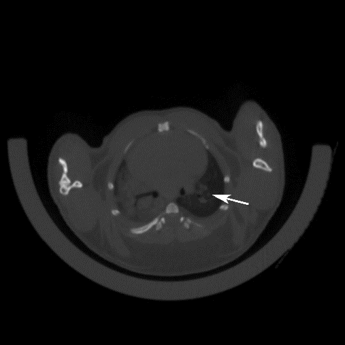

图11 采用气管内注射的方法,将AAV-cre病毒注射到小鼠肺部,在肺细胞中表达Kras G12D致癌基因,从而诱发肺癌发生。3个月后对小鼠肺部进行CT检测,CT结果显示有明显的肿瘤的形成。

图12 Scgb1a1CreERT2/+; KrasG12D/+小鼠肺部CT检测结果。小鼠经腹腔注射玉米油/他莫西芬5次,5个月后对其肺部进行CT检测。